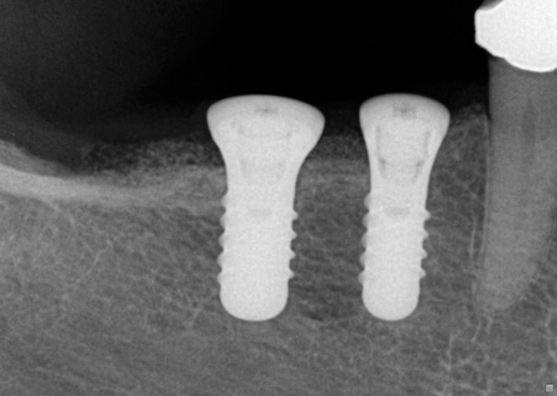

(28.) Postoperative periapical radiograph illustrating 2D implant positions.

Figure 28